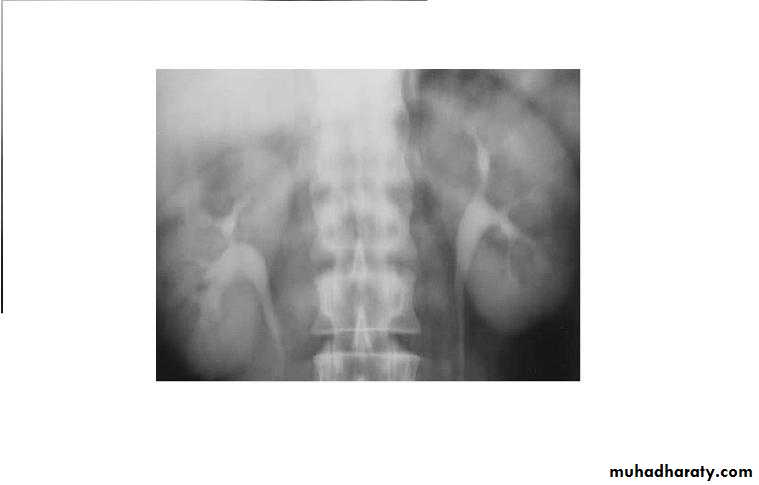

Medially displaced ureters